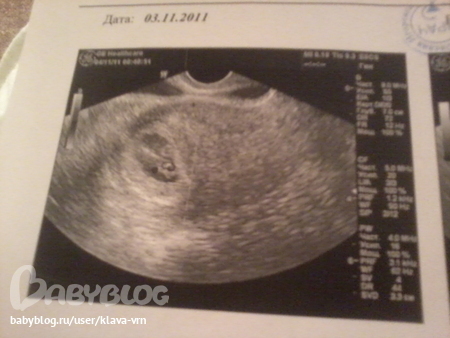

Отслойка ПЯ по узи

Результаты: УЗИ, КТГ, доплера, скринингаПривет! из-за небольшого кровотечения лежала в больниц с угрозой В на 4-5 неделях. Потом все прекратилось и меня выписали. Сказали сходишь на узи, если сердцебиение будет, то значит все ок:) сходила - сердечко бьется, срок 6 нед., развивается нормально. Еще сказали, что отслойка старая осталась, но типа она "уже старая и заживает, но кровить и мазать еще может". Сказали продолжать дома соблюдать постельный режим. Выкладываю фото узи, можете подсказать -где именно отслойка? не со стороны малыша??? а то у узиста забыла спросить:(